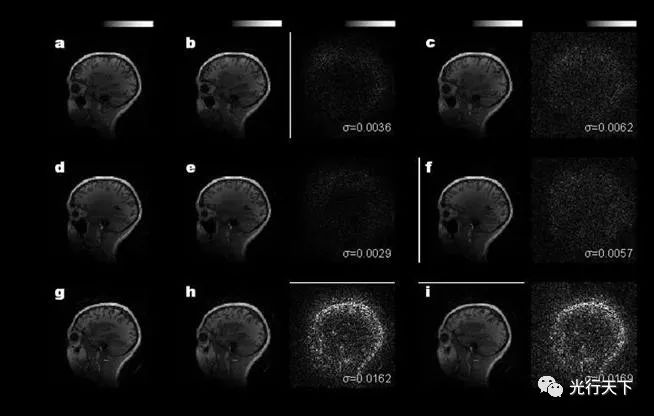

光學(xué)相干點(diǎn)積核芯片重構(gòu)結(jié)果與計(jì)算機(jī)結(jié)果的對(duì)比

本研究中,鄒衛(wèi)文教授團(tuán)隊(duì)利用醫(yī)學(xué)圖像重構(gòu)任務(wù)作為驗(yàn)證,在芯片上成功地運(yùn)行了AUTOMAP(用于通用圖像重構(gòu))神經(jīng)網(wǎng)絡(luò)模型,圖像重構(gòu)的質(zhì)量接近了32位計(jì)算機(jī)的理想水平。該工作不僅推動(dòng)光學(xué)神經(jīng)網(wǎng)絡(luò)研究領(lǐng)域攻克實(shí)際應(yīng)用難題,更為下一代智能計(jì)算技術(shù)提供了新思路。后續(xù)進(jìn)一步提高芯片的器件集成規(guī)模,有望實(shí)現(xiàn)更高速、更低功耗的光學(xué)神經(jīng)網(wǎng)絡(luò)處理器,緩解智能算力需求劇增與傳統(tǒng)硬件算力受限的矛盾。 該工作由上海交通大學(xué)、北京大學(xué)與中科院半導(dǎo)體所合作完成。上海交通大學(xué)為第一完成單位,博士研究生徐紹夫?yàn)榈谝蛔髡?,鄒衛(wèi)文教授為通訊作者。